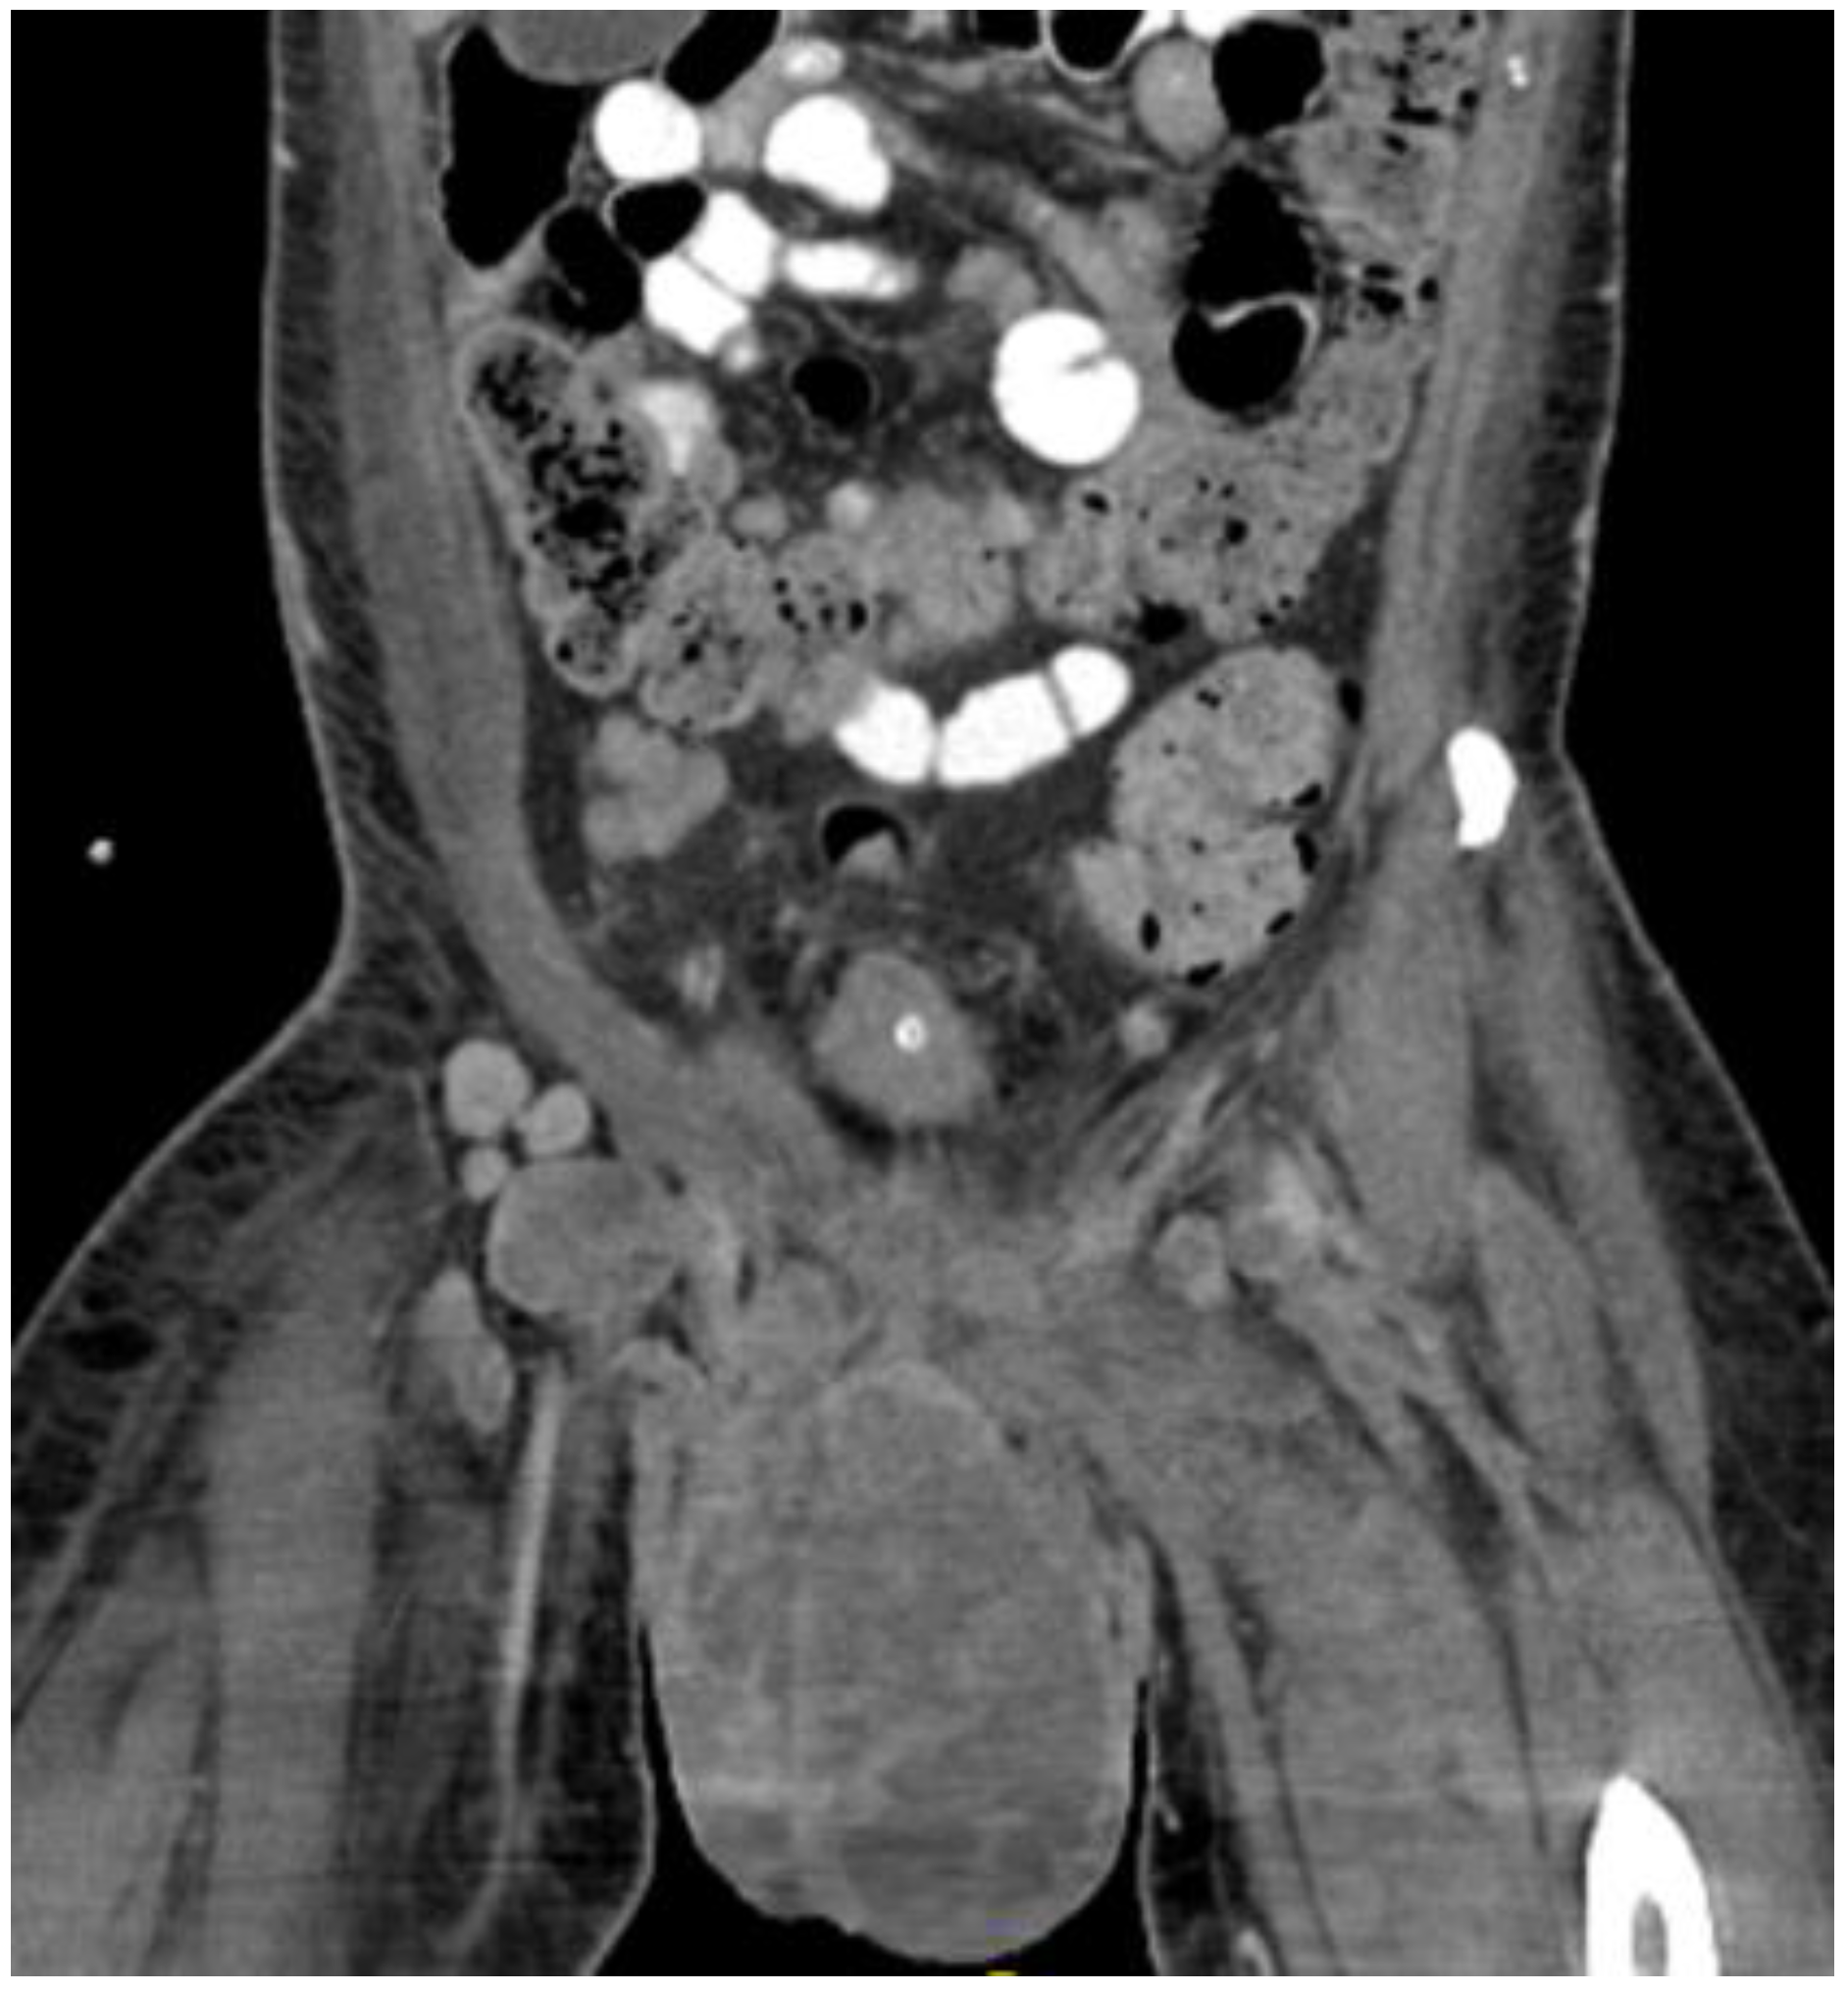

Figure 7.

CT in the coronal view of scrotal mass in the right inguinal lymph node.